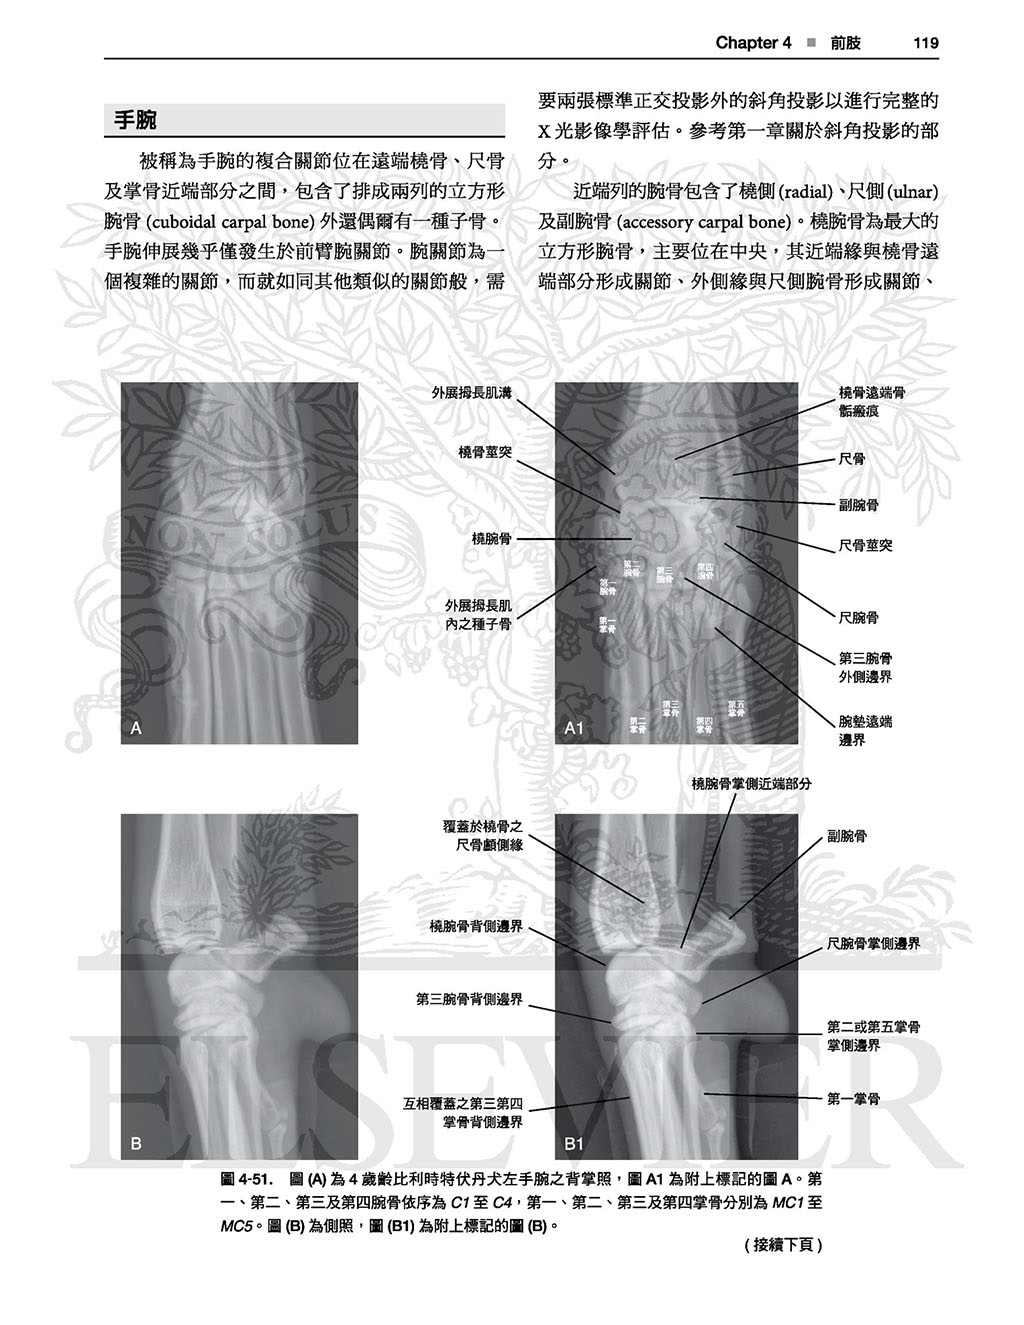

以這本詳盡的圖譜學習犬貓正常放射線解剖學的範圍。精通本書將可使診斷更精確並達到更佳的治療效果!

全書皆為高對比的數位影像,除提供正常影像的深入判讀外,亦提供常見且易被誤判為疾病的正常變異;另外並提供多張電腦斷層影像以強調某些結構之影像在放射線學下顯得如此獨特的原因。

本書不但含有豐富圖片,身體各部份皆附上文字描述以協助讀者了解放射解剖學原則,讀者可舉一反三、甚至能以此理解未包含於本書的正常變異。

.詳盡的文字說明及圖片標示

.未標記的原始圖片及標示後的圖片比對

4前肢, 87

成為專業放射診斷醫師是一條漫漫長路,需要在考到獸醫師執照後最少再四年的學習及各階段的嚴峻考試才能得到學會的專業認證,但是每天進行X光影像判讀的獸醫師中畢竟是只有少數是學會認證的放射診斷醫師,大部分的X光影像判讀是由相較未受到專業指導及臨床訓練的一般獸醫師執行。如同剛開始發展判讀技巧的學生,這些獸醫師應對正常的X光影像解剖學、解剖差異及看似疾病的影像(這些影像被我們這種花費一生在判讀影像的人暱稱為「假象」(takeout))有深厚的辨識度。犬貓中巨大的正常差異令人瞠目,雖然貓較為一致,但犬則有各種不同的形狀及大小,其中還有各種若無法分辨為正常即可能被誤判為疾病的遺傳性差異。除了遺傳性差異外還有因X光拍攝擺位造成的差異,也可能造成正常結構形成無數的造影差異。於專業訓練中,這些觀念會在無數小時的專人指導及訓練下被深深植入,而另一方面未受專業訓練的獸醫師可能在學校時看過一些正常的X光影像解剖學,但伴隨著其他成為一名合格執業獸醫師需要的大量記誦知識後,這些記憶變得模糊。於在學期間不太可能接觸所有臨床上可能遇見的正常範圍及受到擺位影響的影像,因此臨床獸醫師及學生們確實需要一個X光影像的判讀對照標準以進行適當的臨床X光影像學判讀。本書即因此需求而生。於本書中,我們不只指出了基本上犬貓中所有具臨床意義的解剖構之X光影像,也包含可能影響判讀的解剖構造正常差異的例子,若只是單純地標示犬貓各構造的X光影像對於提供具臨床意義的標準並無幫助。此外本書亦包含了關於唯有放射師 能提供的正常解剖描述之內容:以正常影像如何被拍攝步驟影響的方式呈現,雖然本書並非為X光造影擺位的指南,但因具體的操作因素可能對X光影像的影響極大,故為了能進行精確判讀仍帶有部分相關資訊。

最後,本書並不只是單純的圖譜,各身體部位皆有文字描述,因此有助於讀者 理解各構造於X光影像學中如此呈現之原因,且提供了讀者對於X光影像學原理基礎性的理解,有助於對其他正常變異之辨別,雖然可能需要讀者花點心力與圖譜對比使用,但對於判讀能力會有不小的幫助。

專為犬貓正常影像的深入判讀,使診斷更精確達到更佳的治療

以這本詳盡的圖譜學習犬貓正常放射線解剖學的範圍。精通本書將可使診斷更精確並達到更佳的治療效果!

全書皆為高對比的數位影像,除提供正常影像的深入判讀外,亦提供常見且易被誤判為疾病的正常變異;另外並提供多張電腦斷層影像以強調某些結構之影像在放射線學下顯得如此獨特的原因。

本書不但含有豐富圖片,身體各部份皆附上文字描述以協助讀者了解放射解剖學原則,讀者可舉一反三、甚至能以此理解未包含於本書的正常變異。

.詳盡的文字說明及圖片標示

.未標記的原始圖片及標示後的圖片比對

4前肢, 87

成為專業放射診斷醫師是一條漫漫長路,需要在考到獸醫師執照後最少再四年的學習及各階段的嚴峻考試才能得到學會的專業認證,但是每天進行X光影像判讀的獸醫師中畢竟是只有少數是學會認證的放射診斷醫師,大部分的X光影像判讀是由相較未受到專業指導及臨床訓練的一般獸醫師執行。如同剛開始發展判讀技巧的學生,這些獸醫師應對正常的X光影像解剖學、解剖差異及看似疾病的影像(這些影像被我們這種花費一生在判讀影像的人暱稱為「假象」(takeout))有深厚的辨識度。犬貓中巨大的正常差異令人瞠目,雖然貓較為一致,但犬則有各種不同的形狀及大小,其中還有各種若無法分辨為正常即可能被誤判為疾病的遺傳性差異。除了遺傳性差異外還有因X光拍攝擺位造成的差異,也可能造成正常結構形成無數的造影差異。於專業訓練中,這些觀念會在無數小時的專人指導及訓練下被深深植入,而另一方面未受專業訓練的獸醫師可能在學校時看過一些正常的X光影像解剖學,但伴隨著其他成為一名合格執業獸醫師需要的大量記誦知識後,這些記憶變得模糊。於在學期間不太可能接觸所有臨床上可能遇見的正常範圍及受到擺位影響的影像,因此臨床獸醫師及學生們確實需要一個X光影像的判讀對照標準以進行適當的臨床X光影像學判讀。本書即因此需求而生。於本書中,我們不只指出了基本上犬貓中所有具臨床意義的解剖構之X光影像,也包含可能影響判讀的解剖構造正常差異的例子,若只是單純地標示犬貓各構造的X光影像對於提供具臨床意義的標準並無幫助。此外本書亦包含了關於唯有放射師 能提供的正常解剖描述之內容:以正常影像如何被拍攝步驟影響的方式呈現,雖然本書並非為X光造影擺位的指南,但因具體的操作因素可能對X光影像的影響極大,故為了能進行精確判讀仍帶有部分相關資訊。

最後,本書並不只是單純的圖譜,各身體部位皆有文字描述,因此有助於讀者 理解各構造於X光影像學中如此呈現之原因,且提供了讀者對於X光影像學原理基礎性的理解,有助於對其他正常變異之辨別,雖然可能需要讀者花點心力與圖譜對比使用,但對於判讀能力會有不小的幫助。